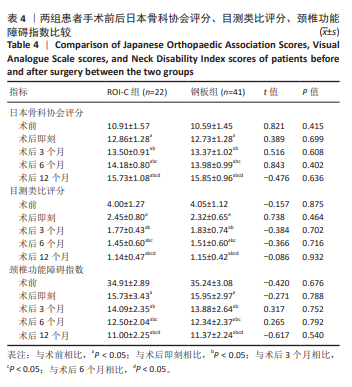

2.6 手术前后影像学评估 两组患者术后C2-7 Cobb角、T1倾斜角,椎间隙高度均较术前显著改善,两组组内不同时间点的C2-7 Cobb角、T1倾斜角,椎间隙高度比较存在显著差异(P < 0.001),而不同分组之间的评分差异无显著性意义(P > 0.05),并且两组在不同时间点的趋势也无显著差异(P > 0.05)。 ROI-C组术后即刻、术后3,6,12个月的C2-7 Cobb角、手术节段椎间隙高度及术后3,6个月的T1倾斜角较术前均显著增加;术后3,6,12个月的C2-7 Cobb角、术后3个月的T1倾斜角均较术后即刻明显增加;术后6个月的C2-7 Cobb角较术后3个月明显增加,差异有显著性意义(P < 0.05)。钢板组术后即刻、术后3,6,12个月的C2-7 Cobb角、手术节段椎间隙高度及术后即刻、术后3,6个月的T1倾斜角均较术前明显增加;与术后即刻相比,钢板组术后3,6,12个月的C2-7 Cobb角及术后3,6个月的T1倾斜角均明显增加;术后6个月的C2-7 Cobb角较术后3个月明显增加,术后12个月的T1倾斜角较术后3个月明显减小;术后12个月的T1倾斜角较术后6个月明显减小,差异有显著性意义(P < 0.05)。见表5。"